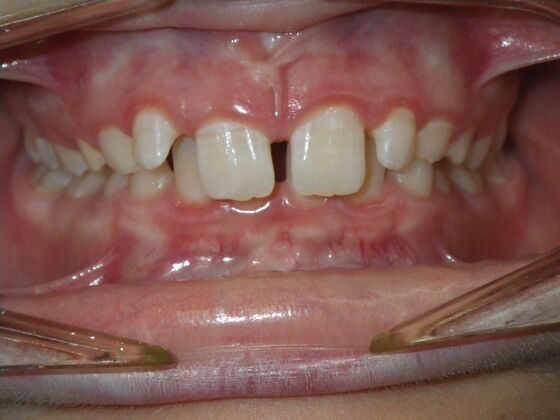

This patient does not like his anterior deep bite and the flaring of the right lateral incisor as well as anterior spacing. The solution was to correct his Class II molar relationship, Division II and deep anterior bite and close spacing as much as possible with addition of composite restorations on distals of lateral incisors. We began with utility archwires, eventually correcting Class II molar with distalizing appliance, and continued with final tip and torque. All that is left now is to ad composite to distals of upper lateral incisors.